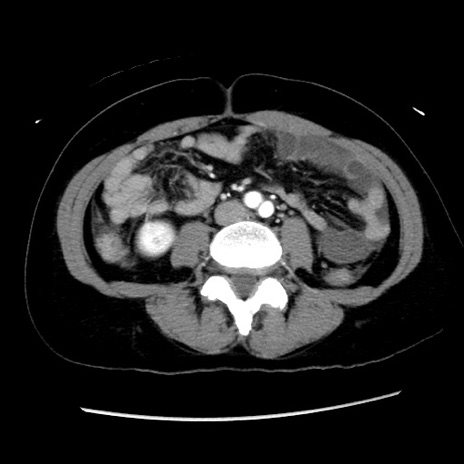

症例10(横断像)

【症例】 50歳代女性

【主訴】 腹痛

【現病歴】前日生レバーを食べた。今朝に排便あり。 昼前に突然発症の腹痛を生じ、当院救急外来を受診した。

【既往歴】 子宮筋腫にてで子宮全摘後

【身体所見】 意識清明、腹部:平坦、軟、下腹部やや左を中心に圧痛・反跳痛あり、筋性防御あり

【データ】WBC 7800、CRP 0.07